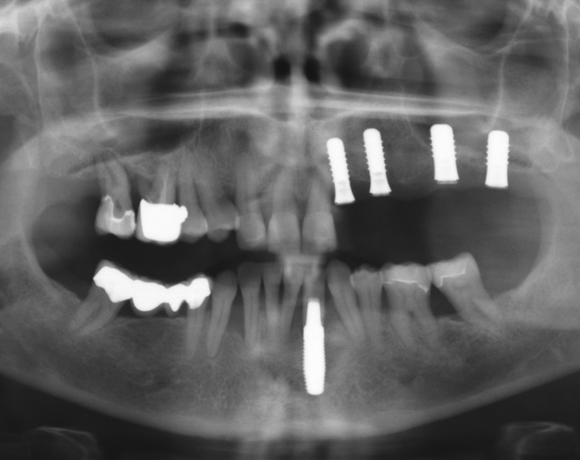

Zeramex P Implantate für die Zähne 22-27

Ein Projekt aus dem Jahr 2013

Bei dieser Patientin mussten die Zähne 22,26 und 27 aus parodontalen Gründen entfernt werden. Nach Extraktion der Zähne 22 und 26 wurden sofort in die Extraktionsalveolen die Implantate gesetzt. Zahn 27 war bereits sechs Monate zuvor extrahiert worden und die Knochenwunde gut ausgeheilt. Das geringe Knochenangebot wurde mit einem internen Sinuslift ausgeglichen. Im Bereich des Zahnes 23 wurde noch ein weiteres Implantat gesetzt. Da der Zahn 12 nicht angelegt und die Symetrie auf dieser Seite gestört war, wurden die Zähne 11 und 13 mit Teilkronen versorgt, um die Lücken zu schließen der Zahn 13 zu 12 umgebaut.